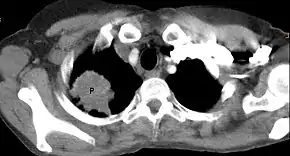

| Chest radiograph showing a Pancoast tumor (labeled as P, non-small cell lung carcinoma, right lung), from a 47-year-old female smoker. | |